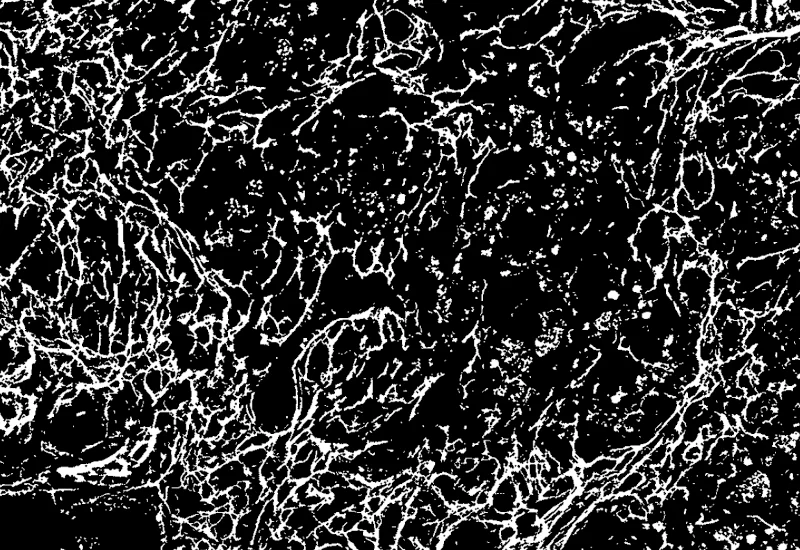

IHC Extracellular Filaments

Detect nuclei and extracellular filaments in IHC-stained sections, and quantify nuclei number, total filament area, and filament length.

The IHC Extracellular Filament App detects nuclei as well as extracellular filaments stained with specific markers. It outputs the number of nuclei, the total gilaments area and the lenght of the filaments.

Filament detection mask

Filament detection